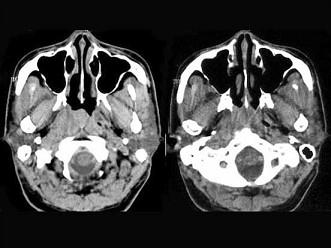

问题 男,52岁,右耳鸣两月余,伴鼻塞,CT如图所示,应诊断为 ( )

选项 A、鼻咽癌 B、鼻咽部慢性炎症 C、鼻咽纤维血管瘤 D、增殖体肥大 E、鼻咽淋巴瘤

答案 A